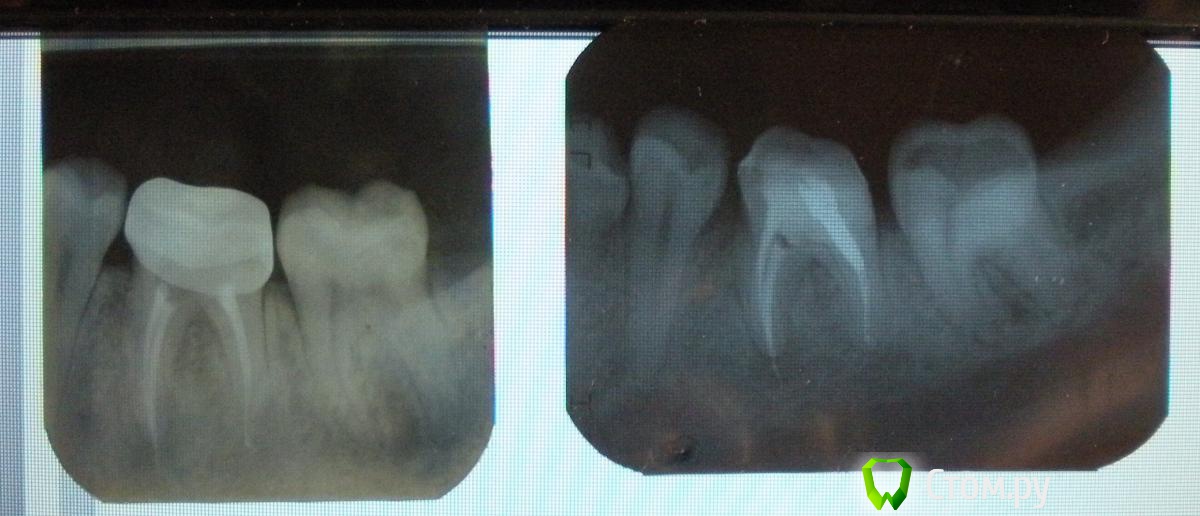

Наташа П. Опубликовано 8 мая, 2014 Автор Поделиться Опубликовано 8 мая, 2014 когда сделаны снимки?Первый в январе, второй вчера Ссылка на комментарий

Наташа П. Опубликовано 8 мая, 2014 Автор Поделиться Опубликовано 8 мая, 2014 На первом снимке зуб под старой коронкой, на втором уже перепломбирован, под временной коронкой Ссылка на комментарий

red_butler Опубликовано 8 мая, 2014 Поделиться Опубликовано 8 мая, 2014 снимки плохого качества, но похоже требуется повторное лечение корневых каналов Ссылка на комментарий

red_butler Опубликовано 8 мая, 2014 Поделиться Опубликовано 8 мая, 2014 а одном корне воспалительный очаг, если не перелечить - зуб потеряете 1 Ссылка на комментарий

red_butler Опубликовано 8 мая, 2014 Поделиться Опубликовано 8 мая, 2014 А очаг на корне где нет штифта? да Ссылка на комментарий